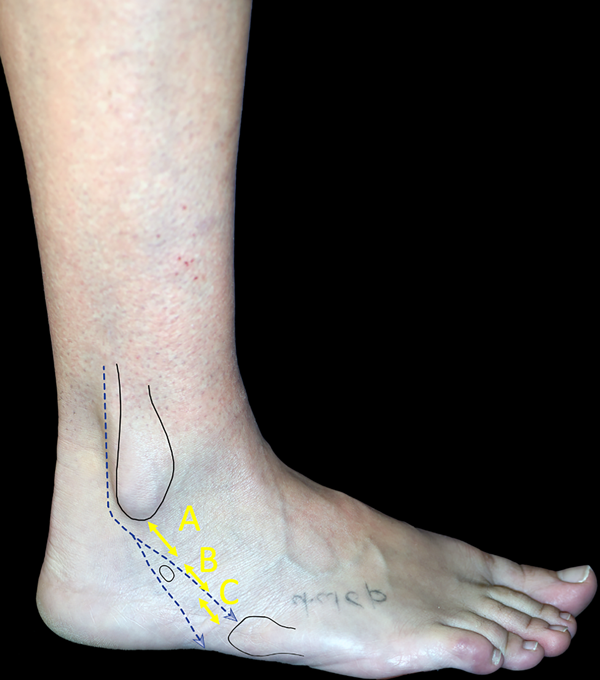

Las roturas del TPL fueron clasificadas por Brandes y Smith según la zona anatómica donde ocurren, descriptas como zonas A, B y C.13,14 La zona A se extiende desde la punta de la fíbula hasta el tubérculo peroneo; la zona B va desde este punto hasta el límite inferior del retináculo peroneo inferior y desde el retináculo peroneo inferior hasta la escotadura cuboidea es la zona C; el 77% de las roturas ocurren en la zona C (fig. 4).14,15

Figura 4: Clasificación topográfica de lesiones del TP. Zona A) Desde la punta de la fíbula hasta el tubérculo peroneo. Zona B) Desde el tubérculo peroneo hasta el límite inferior del retináculo peroneo inferior. Zona C) Desde el retináculo peroneo inferior hasta la escotadura cuboidea.